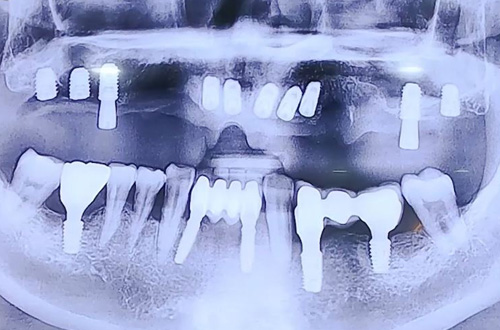

윗니 전체 임플란트 사례

22-11-23 더365치과

BEFORE

위 앞니의 브릿지 보철이 길게 사용된 상태에서,

윗니가 거의 빠지기 직전인 심각한 상태로 내원하신 환자분입니다.